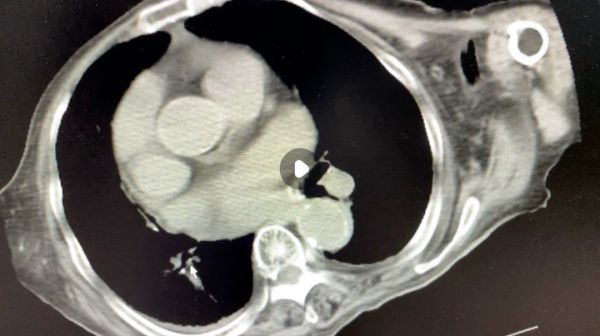

患者,女,90 岁,反复肠梗阻入院,既往心梗、糖尿病、脑梗等病史,一般情况差,家属就没积极处理,禁饮食几天,就通了回家,一般一个月来一次。

CT 如下: